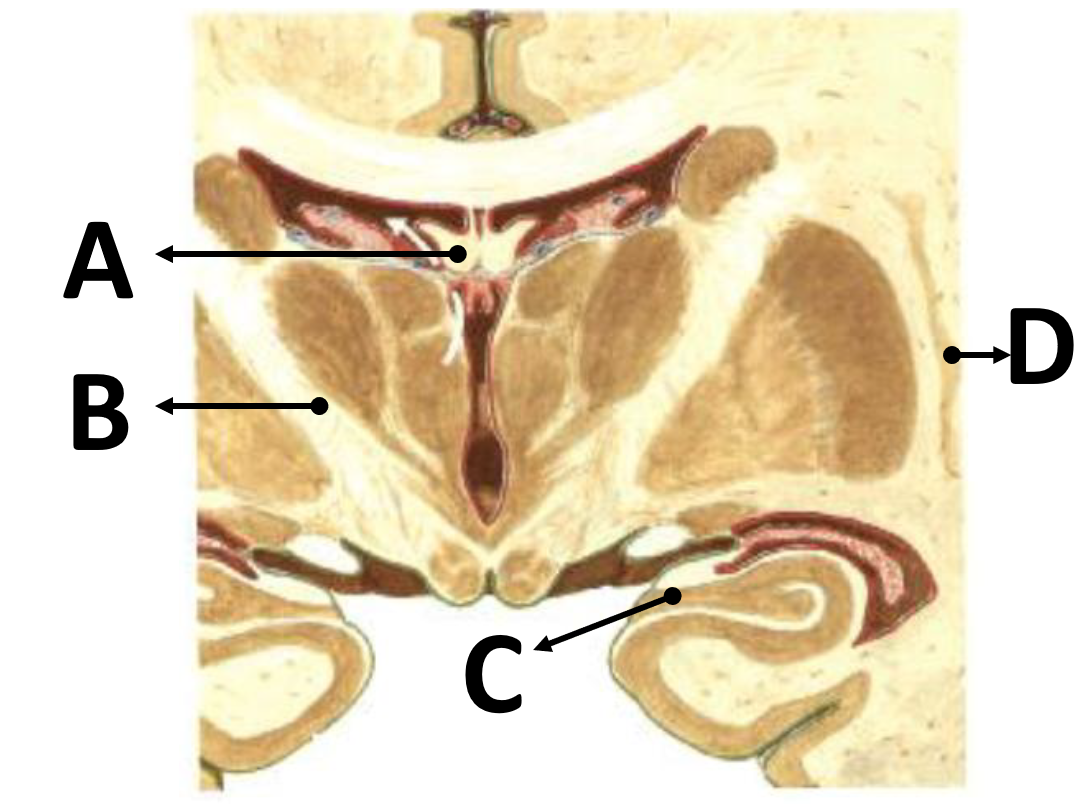

el emparejamiento según corresponda con las estructuras señaladas en la imagen: